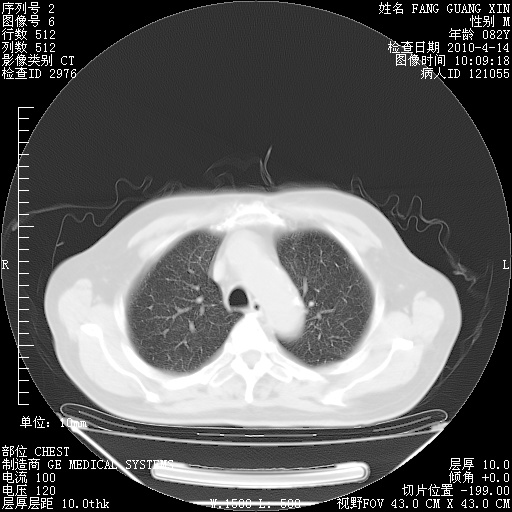

肺部CT平扫未见异常。